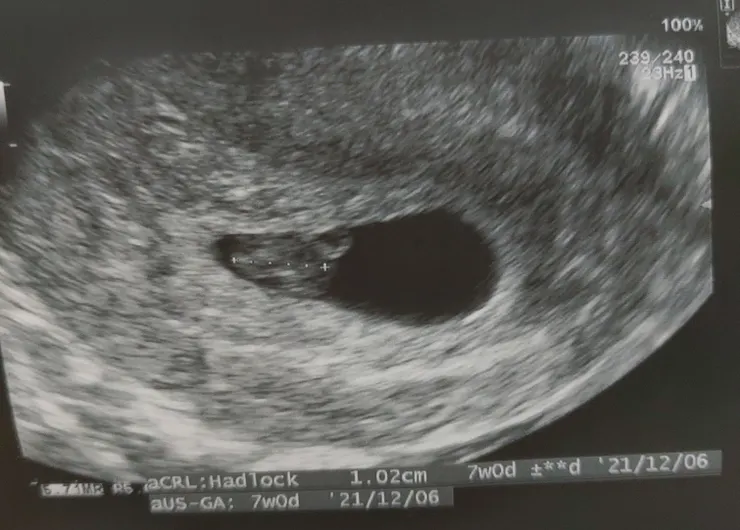

我在三月底的禮拜一晚上確定懷孕了,推算才4-5週,只看得到胚囊,胚胎、心跳啥都沒有,得繼續等待跟觀察身體狀況。